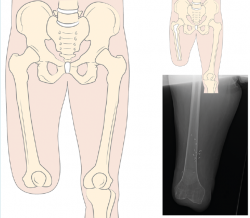

Siempre que la viabilidad de una amputación TT no sea posible, debemos considerar la DR antes que la amputación TF, donde la preservación de los cóndilos femorales facilita la adaptación de un encaje con apoyo distal del muñón (Figura 1). Clínicamente, el apoyo distal es la ventaja más importante en las DR con respecto a la amputación TF, ya que permite transferir directamente la carga distal al muñón femoral y, de este modo, aumentar la independencia en la marcha y reducir el consumo de oxígeno(6,7).